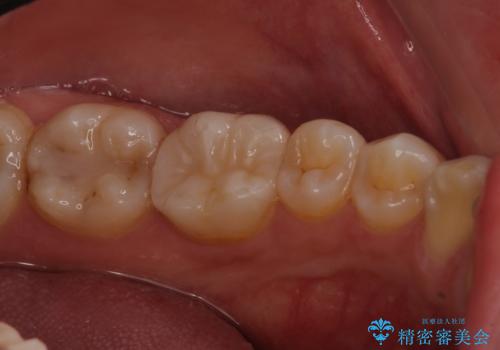

- 左下奥歯の銀歯のつめものがとれたことを主訴にご来院された患者様です。

1番奥の歯のセラミック治療をご希望されましたが、レントゲンなどの診査の結果、大きな虫歯などもありませんでした。

それよりも奥から2番目の歯のほうが、適合不良の銀のつめものが入っており、大きな虫歯が疑われました。

虫歯の大きさや形を加味して、1番奥を保険治療、奥から2番目をセラミック治療で行うことになりました。

ご来院当初、患者様は1番奥歯のセラミック治療をご希望されてました。しかし、しっかり診査をして1本手前の歯を治療した方が良いとご提案させて頂きました。